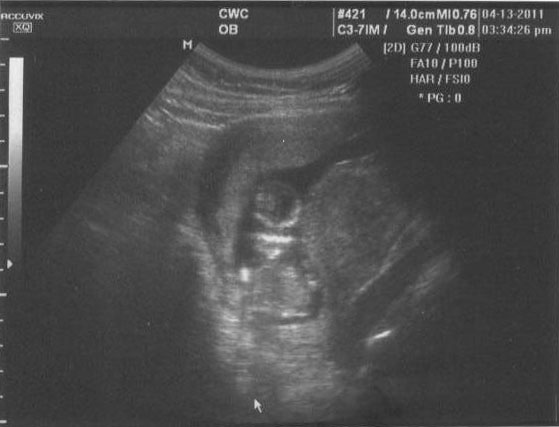

We did the first trimester screening today, which included an in-depth ultrasound. Fox hadn't yet seen the high quality images that we get at the Perinatal Center as compared to the OBGYN's office, so he was in awe at all that we could see.

This is how the baby was positioned at the start of the ultrasound: upside down and very contentto be so. Kind of cute, yes? It kept trying to get back into this position during the whole process.

After some poking, prodding and otherwise trying to convince the kid to get into the position the technician needed, it did eventually cooperate, for a little while. When it tried to change positions, the technician would poke and prod some more. We laughed when we saw a little tongue sticking out. A sign of things to come perhaps?

As indicated, these are the kid's feet. We got a decently good look at the feet and legs, as well as the arms, hands and brain. The arms were crossed, like an Egyptian mummy. During the whole ultrasound, the kid was practicing swallowing, which looked like a bad case of the hiccups.